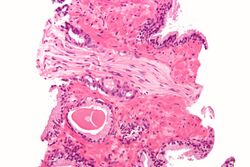

Micrograph showing a prostate cancer (conventional adenocarcinoma) with perineural invasion. H&E stain.

A histopathologic diagnosis mainly includes assessment of whether a cancer exists, as well as any subdiagnosis, if possible.[150] Histopathologic subdiagnosis has implications for the possibility and methodology of Gleason scoring.[151] The most common histopathological subdiagnosis is acinar adenocarcinoma, constituting 93% of diagnoses.[152] The most common form of acinar adenocarcinoma, in turn, is "adenocarcinoma, not otherwise specified", also termed conventional, or usual acinar adenocarcinoma.[153]